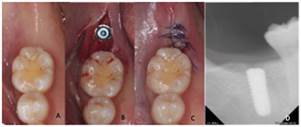

Colocación de implante dental cuadrante IV

Previa asepsia y antisepsia con yodopovidona, se aplicó anestesia local (articaína 4% con epinefrina 1:100000) en fondo de saco del 4.7 para bloquear el nervio alveolar inferior y se procedió a la colocación de implante de 5mm x 11.5mm (Hiossen) en 4.7 en adecuada tridimensionalidad planeada y siguiendo el protocolo de fresado recomendado por el fabricante (Fig. 2).